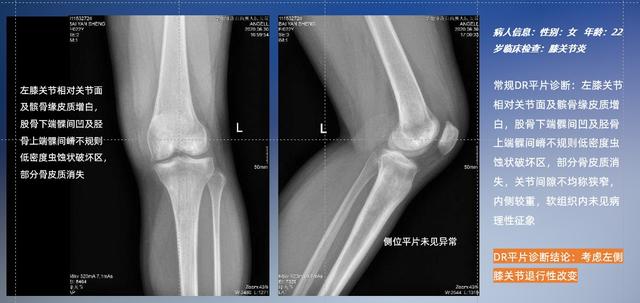

以膝关节疾病检查为例,膝关节在解剖学意义上是一种较为复杂的最大关节,由胫骨上端、股骨下端及髌骨组成。在股骨与胫骨的关节面之间存在两块半月板,分别处于内侧、外侧。膝关节的运动主要为伸、屈,在半屈位时可进行小幅度的旋外、旋内运动。随着现代人们体育生活以及肥胖的增加,膝关节疾病出现高发趋势,特别是关节磨损、膝关节炎与骨关节炎等关节退行性改变,长时间的内翻负荷会造成内侧关节软骨、骨性关节面的磨损。目前针对此类疾病的检查主要为平片下的负重位检查、CT检查以及MRI检查,相较于非负重位检查,负重位检查能更加真实反映膝关节结构中胫骨、股骨、髌骨实际对位关系和关节面的形态特征及关节间隙大小,对膝关节骨关节病诊断准确率高。

普通平片扫描与WR-3D扫描前后诊断结果对比

与此同时,数字化X线摄影技术相较于CT和MRI来说,能快速获取真实、直观、满足临床需要的影像。DR的图像具有图像层次丰富、空间分辨力高、影像边缘锐利清晰、密度分辨力高级细微结构表现出色等特点,针对膝关节解剖结构数字化X线摄影技术应用价值很高,尤其是是对骨小梁与骨皮质的显示非常清楚。在负重位状态下,数字化X线三维摄影扫描与重建,能够更好的呈现受检者关节受力改变的状态。388vip太阳集团科技创新的WR-3D动态三维数字化X线摄影技术,通过数字化X线摄影完成三维扫描并重建三维影像信息,包括MPR多平面重建、MIP重建以及VR绘制。扫描时间短,剂量相较于CT设备大幅缩减,同时成本更低,在临床诊断以及医疗方案制定中具有极大的价值意义。相较于普通平片下的负重位扫描,负重位动态三维扫描摄影技术能够避免二维状态下的组织结构重叠、密度分辨率不足、组织解剖结构难以分辨等问题,WR-3D支持多角度的动态三维摄影观察,能全面的呈现被检查部位在多个角度下三维影像信息,极大的减少了二维负重位检查的漏诊率。